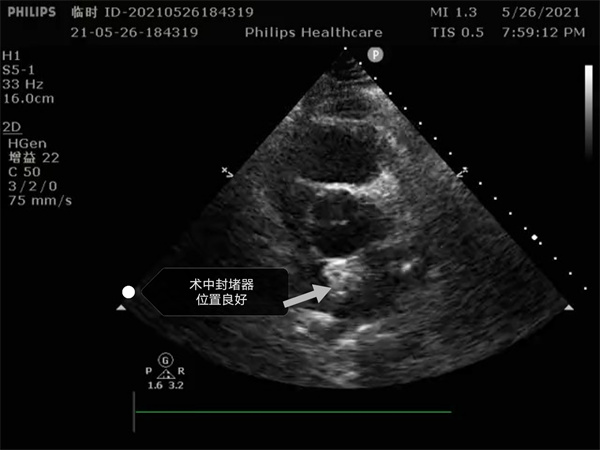

尤其是患者是個三房心,正常的人是有二個心房,這是一種少見的先天性心臟畸形, 如何在三房心把這個洞堵住,而且不影響心臟正常結(jié)構(gòu),是這個手術(shù)難點。沈主任組織全科進行術(shù)前討論,5月26日下午5點開始手術(shù),導(dǎo)絲如何在不規(guī)則的只有米粒大小的卵圓孔里通過,鞘管如何通過,如何進入卵圓孔連接的副房,避免封堵器夾住隔膜,這些難點在術(shù)中被沈主任團隊一一化解,手術(shù)歷時二小時,隨著封堵器成功釋放,導(dǎo)管室外響起來熱烈的掌聲。

就這樣三房心合并卵圓孔未閉發(fā)生過三次腦梗的患者,在安康市中心醫(yī)院心內(nèi)科導(dǎo)管室成功進行了國內(nèi)第二例介入封堵手術(shù)。